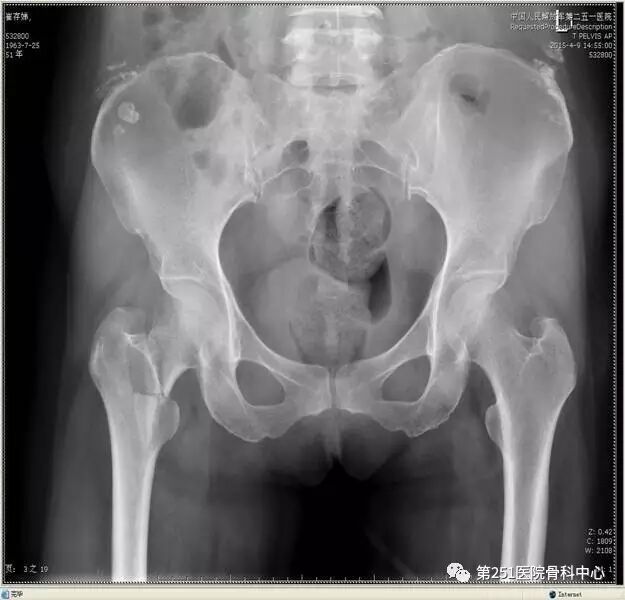

病例4:女性,车祸伤,同侧股骨、股骨颈合并胫腓骨骨折。

![]()